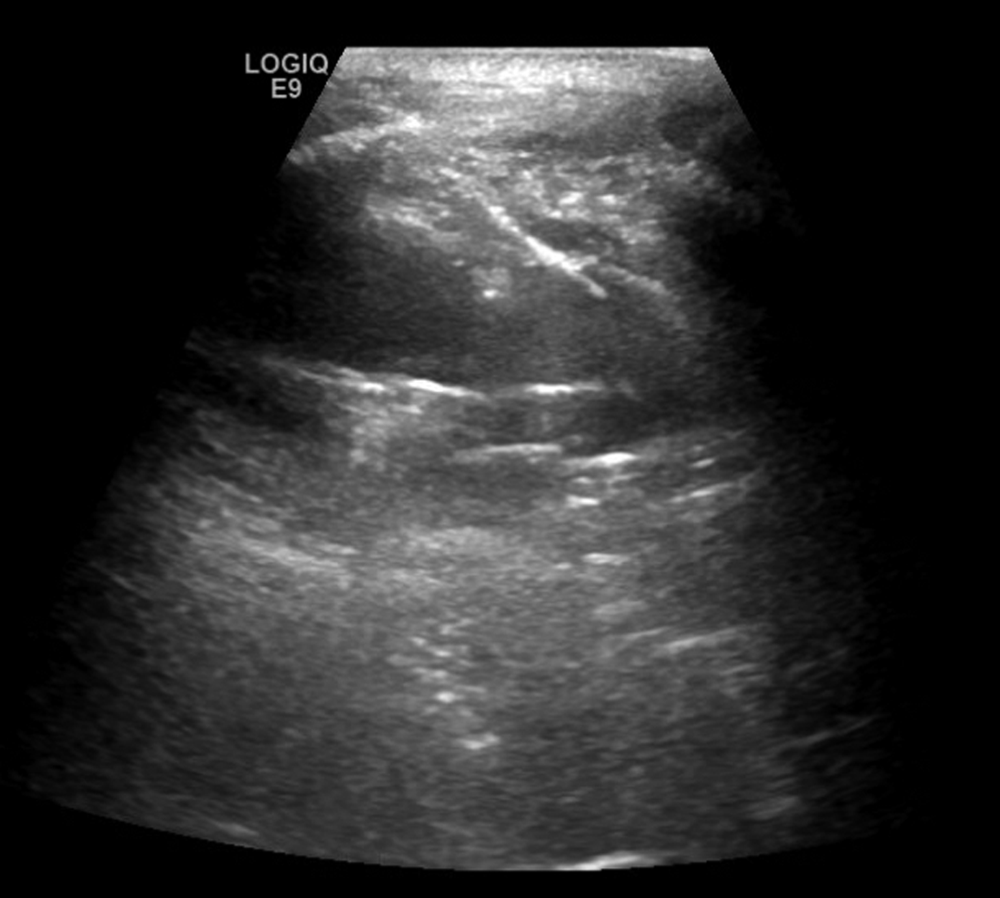

Yamamoto N, Watanabe T, Yamada K, et al. Efficacy and safety of ultrasound (US) guided percutaneous needle biopsy for peripheral lung or pleural lesion: comparison with computed tomography (CT) guided needle biopsy[J]. J Thorac Dis, 2019, 11(3): 936-943. DOI: 10.21037/jtd.2019.01.88.

Jarmakani M, Duguay S, Rust K, et al. Ultrasound versus computed tomographic guidance for percutaneous biopsy of chest lesions[J]. J Ultrasound Med, 2016, 35(9): 1865-1872. DOI: 10.7863/ultra.15.10029.

Park J, Park B, Lim JK, et al. Ultrasound-guided percutaneous needle biopsy for small pleural lesions: diagnostic yield and impact of CT and ultrasound characteristics[J]. AJR Am J Roentgenol, 2021, 217(3): 699-706. DOI: 10.2214/AJR.20.24120.